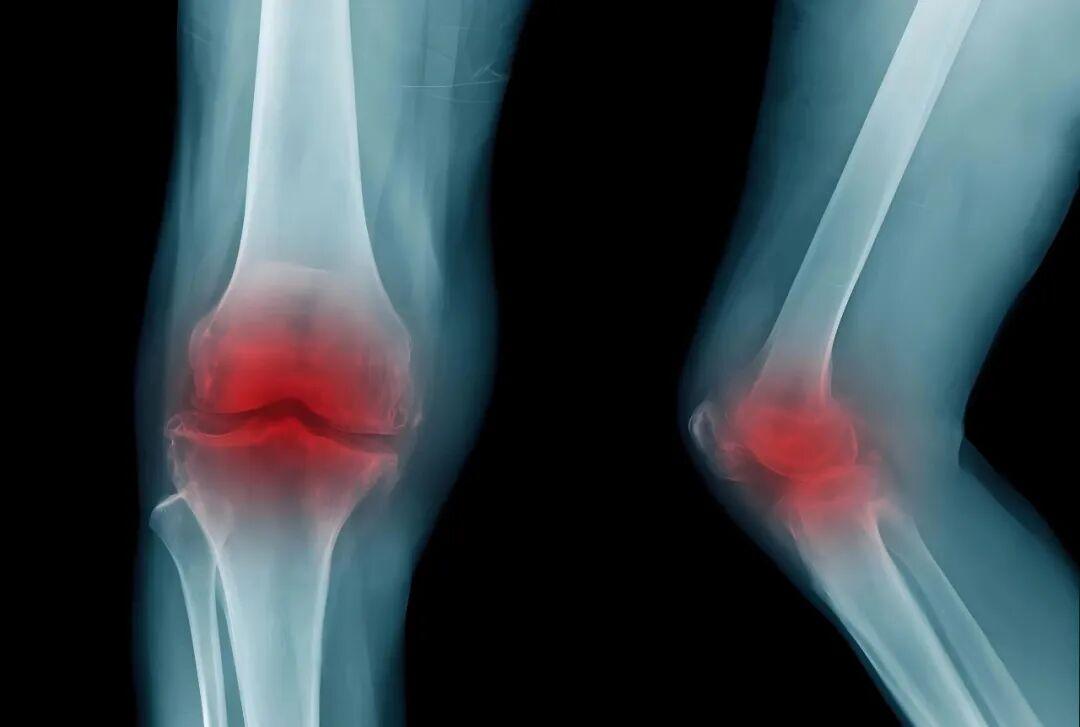

1.膝关节:作为人体主要承重关节,磨损概率最高。典型表现为:上楼梯、爬坡时疼痛加重,平地行走缓解;久坐或晨起后关节僵硬,活动3-5分钟后改善;严重时可能出现关节肿胀、活动时弹响明显。